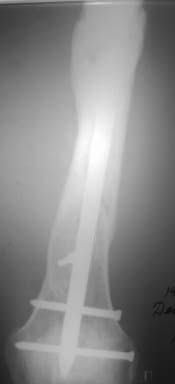

Re: Неправильно сросшийся перелом голени

Александр Николаевич, к сожалению больной не является на контрольные осмотры. Я последний раз видел больного, когда прошло 7 месяцев после операции БОС. У него все хорошо. Каких либо жалоб и ограничений в нагрузке нет. Высылаю снимки до операции и последние снимки.